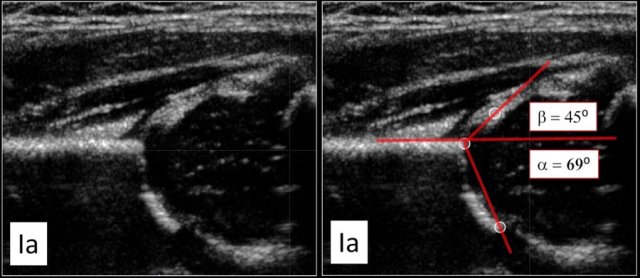

Type Ia

This examination shows a good morphology of the bony acetabular roof with a sharp angular bony rim.

No problem here in depicting the lateral rim of the bony roof of the acetabulum.

There is nice coverage of the femoral head by the cartilaginous roof and the labrum.

The alpha angle is above the 60 degrees and the beta-angle is way below 55 degrees.